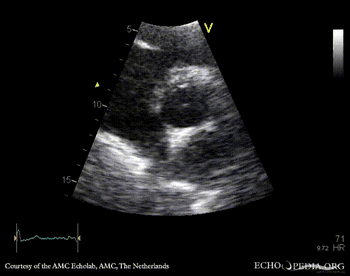

E00416.gif E00417.gif

PLAX: vegetation on aortic valve PSAX: vegetation on aortic valve